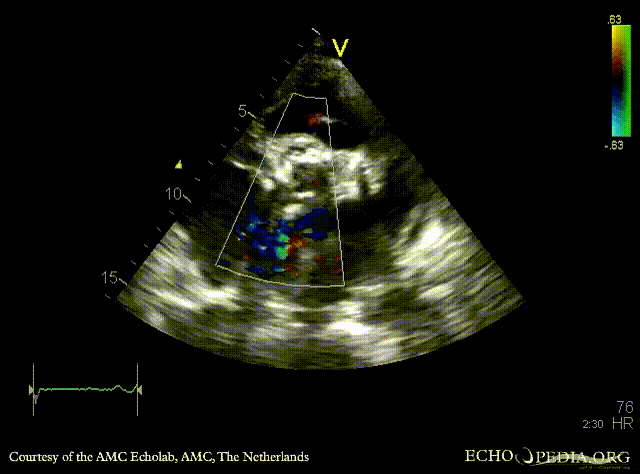

| A3CH: Color Doppler, mild aortic regurgitation